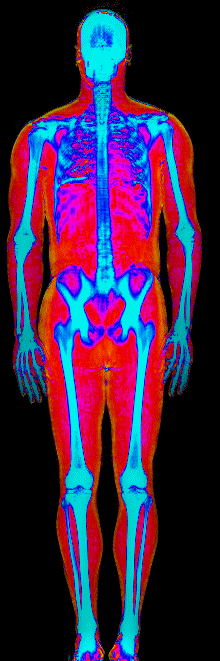

What Fat Loss Looks Like on a DEXA Scan

Lost 30.2 lb of fat, gained 3.9 lb lean · 240 → 214 lb · Age 43

Lost 27.9 lb of fat · 225 → 191 lb · Age 40

Lost 23.7 lb of fat · 186 → 155 lb · Age 34